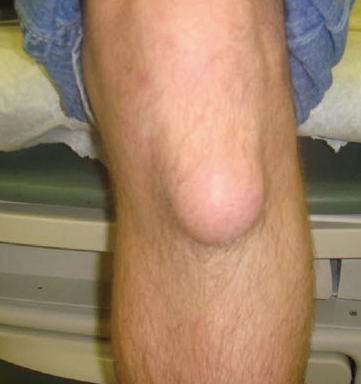

- Prepatellar bursitis, "housemaid's knee"

전슬개 점액낭염(housemaid's knee)